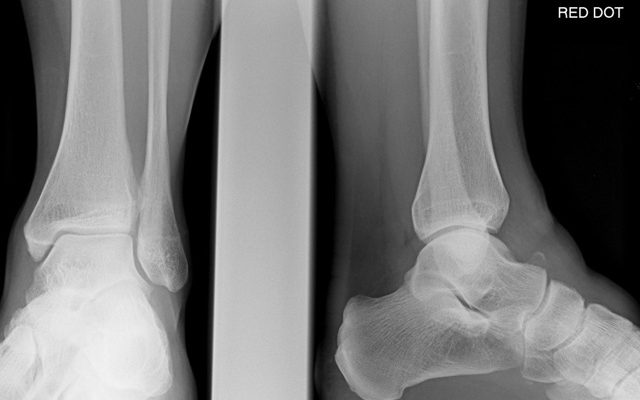

Помимо общего осмотра пациенту требуется комплексная диагностика. Для более тщательного изучения места перелома делают рентгеновские снимки. Вашему врачу потребуются боковые и передние снимки для подтверждения диагноза. Рентген делает шейку бедра полностью видимой.

Проекция Canale производится в зоне максимального эквинуса. Пронация — 15 градусов, снимок сделан под углом 75 градусов. Если изображение нечеткое или рентгенограмма не может быть сделана, выполняется компьютерная томография.